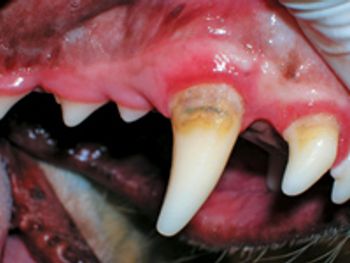

Make sure you know the best way to treat these discolorations that can signify severe disease.